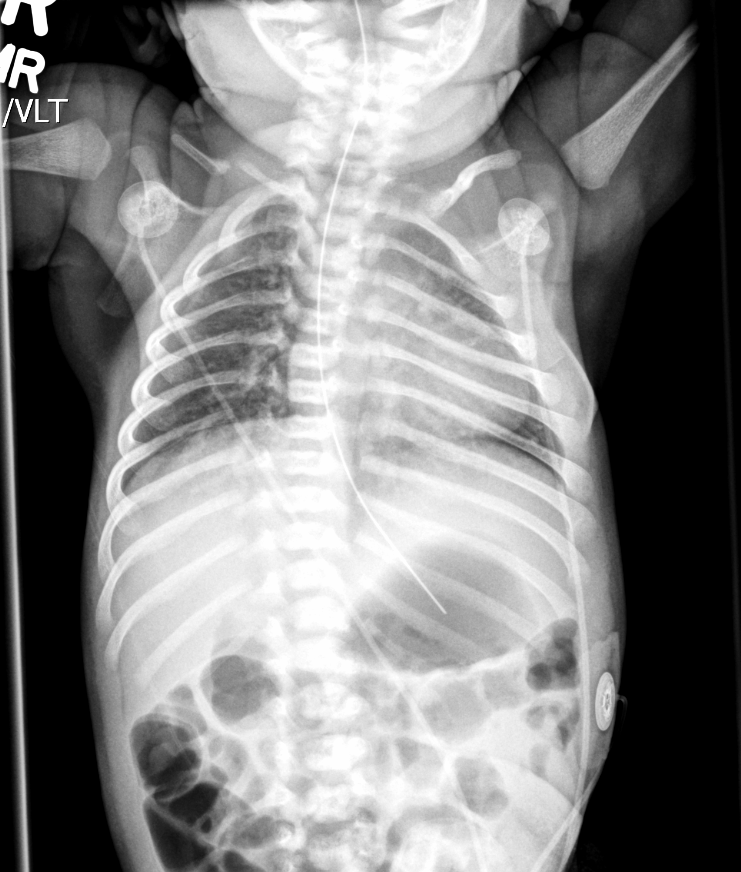

Info Images Findings Impression Reco/Acuity Case Images View Images / Launch Visage Case Notes History 2-month-old presents with decreased right arm movement, increased fussiness, and increased sleepiness for 2 days. Suspected non-accidental trauma. Exam Skeletal survey Prior Study none Dicom View Reference Material

Section 1 Submit Findings CB1550 Findings Skeletal Survey - Technique Check Skull AP/Lat Yes No Cervical and Thoracolumbar spine Yes No Chest X-Ray Yes No Ribs – Left/Right Oblique Yes No Abdominal X-Ray Yes No Pelvis with both hips Yes No Bilateral Humerus, Forearm, Hand Yes No Bilateral Femur, Tibia/fibula, feet Yes No Any additional lateral views of the extremities Yes No The exam is over or under penetrated. Yes No The exam may or may not be limited by overlying structures or soft tissues, body habitus, patient positioning, support devices, or motion. Yes No The area of concern is indicated by the patient, technologist, or care provider. Yes No The area of concern is included on the exam. Yes No Soft Tissues There is soft tissue swelling, indistinctness of fat/muscle planes, gas, or laceration in the area of clinical concern. Yes No There is an effusion, fat pad displacement, or fat fluid level. Yes No There is a radiodense or lucent foreign body. Yes No There are other densities, calcifications, post-surgical changes, or support devices in the soft tissues. Yes No Any support lines/tubes. Yes No Bone There is a break or interruption of the continuity of the cortical or cancellous bone. Yes No There is overriding of the trabeculae with apparent sclerosis. Yes No There is displacement of a fracture fragment. Yes No There is bowing of the bone in addition to the fracture at the apex of the bowed bone concerning for the greenstick. Yes No There is a spiral fracture of the leg concerning for toddler’s fracture. Yes No There is abnormal angulation or bulging of the cortical surface relative to the normal cortex which could be from a buckle or torus fracture. Yes No There is a displaced fragment which may be from avulsion by a tendon, ligament, or joint capsule or from a comminuted or other fracture. Yes No The stress trabeculae or other trabeculae of the cancellous bone are interrupted or otherwise abnormal. Yes No There is subperiosteal or endosteal reaction which could indicate a healing or subacute fracture or other abnormality. Yes No There is hard/soft callus formation. Yes No There is remodeling of the bone. Yes No There is a corner fracture or metaphyseal lesion that could be from nonaccidental trauma. Yes No There are multiple fractures of different ages. Yes No There are vertebral body/spinous process fractures. Yes No There are rib fractures. Location - posterior or lateral. Yes No There is scapular/sternal fracture. Yes No There are fractures of the digits. Yes No There are wormian bones. Yes No There are intrasutural bones. Yes No There is metaphyseal abnormality (lucencies, increased density, erosion) which may be from something other than injury such as stress, metabolic disease (e.g. rickets with loss or distortion of the zone of the provisional calcification), neoplasm (e.g. leukemia), heavy metals, inflammation, or infection. Yes No There are metaphyseal spurs. Yes No There are bony deformities involving multiple bones. Yes No The bones are gracile. Yes No There are non-healing fractures. Yes No There is/are focal or multifocal lytic/lucent, blastic/sclerotic or mixed density lesion(s) or other abnormality. Yes No Overall bone density is increased or decreased with or without thinning or thickening of the cortical or cancellous bone. Yes No Growth plates, ossification centers, apophyses The growth plate(s) is/are abnormal. Yes No There is widening of the physis from a fracture with or without displacement of the epiphysis (Salter-Harris I). Yes No There is a fracture through the physis which then extends into the metaphysis with or without angulation or displacement (S-H II). Yes No There is a fracture through the physis which then extends into the epiphysis and is intra-articular, with or without angulation or displacement (S-H III). Yes No There is a fracture through the metaphysis, physis, and epiphysis which extends into the joint space with or without angulation or displacement (S-H IV). Yes No There is narrowing of the physis from a compression fracture (S-H V). Yes No The apophysis, epicondyle, secondary ossification center, or accessory ossicle is displaced or otherwise abnormal. Yes No The ossification centers are underdeveloped. Yes No Joints and alignment There is an effusion, fat pad displacement, or fat fluid level. Yes No The epiphysis or subchondral bone is fractured, interrupted, flattened, compressed, impacted, displaced, or otherwise abnormal. Yes No There is an intra-articular loose body or chondrocalcinosis. Yes No The joint is widened, narrowed, dislocated, malaligned, or incongruent. Yes No There is pseudoarthrosis. Yes No Other findings There are developmental changes or other anatomic variants or other existing conditions that may or may not be contributing to symptoms which can or should be further evaluated non-emergently or are otherwise incidental. Yes No The remainder of the exam is abnormal for age. Yes No The lungs show focal airspace opacity. Yes No There is pneumothorax. Yes No There is organomegaly. Yes No There is intra-abdominal calcification. Yes No There is displacement of the bowel loops. Yes No There is free intraperitoneal air. Yes No The bowel loops are dilated/obstructed. Yes No There is paraspinal soft tissue abnormality. Yes No